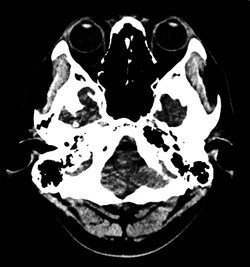

頭部CT

X線を使用する撮影ですが、細いX線ビームを回転しながら出してそれをコンピュータ画像処理したものです。

スライス番号は、すぐ下のCT画像に対応しています。上段の図をクリックすると下段のCT画像が拡大して見られます。